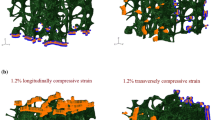

However, studies on human vertebrae have reported more complicated failure phenomena. In thoracolumbar vertebrae loaded in either axial compression or axial compression with anterior flexion, the highest strains within the vertebral body as it reaches its yield and then ultimate points are observed at or near the vertebral endplates, even though these are not the locations of lowest density or least robust architecture [16•, 42] (Fig. 3). Consistent with these findings, regression models that use the density of the endplate region as well as the average density of the entire vertebral body to predict vertebral strength outperform those that use only the average density [44]. In slight contrast, a separate study on thoracolumbar vertebrae found that permanent deformations (assessed by measuring changes in trabecular spacing) induced by a compressive overload and subsequent fatigue loading were most pronounced in the mid-transverse third of the vertebral body followed by the superior third [15]. This apparent discrepancy could suggest differences in failure mechanisms between monotonic and fatigue loading and could also be due to differences in the period of observation. Whereas the fatigue study examined deformations after induction of a fracture severe enough to be observed in radiographs, the studies using monotonic loading quantified displacement and strain fields at or before the ultimate point, which is earlier in the failure process. As the failure process proceeds, the regions of largest deformation at a given point in time can change [16•].

a Strains incurred on the surface of the L1 vertebral body during compression to yield, as measured by digital image correlation [42]. Each row shows a different vertebra. (Used with permission from Wolters Kluwer). b Strains incurred in 27 different regions of the L1 trabecular centrum during compression to yield, as measured by digital volume correlation [16•]. The color of each region corresponds to the median value over n = 26 vertebrae, while the number that labels each region is the interquartile range over all vertebrae with the same units and on the same scale as the median values. *Difference between transverse planes. c Displacements incurred throughout the T8 vertebral body (representative specimen) during compression to just past the ultimate point, as measured by digital volume correlation (left column: top panel shows the microCT rendering before (gray) and upon (blue) loading to just past the ultimate point; bottom panel shows displacements) and as predicted by QCT-based FE simulations for four different types of boundary conditions (middle and right columns) [43]: using displacements measured by digital volume correlation across the endplates (“Experimentally Matched FE”); using uniform displacement boundary conditions (“Idealized FE”); using force boundary conditions calculated from distributions of intradiscal pressure averaged over intervertebral discs (IVDs) at different stages of degeneration (“IVD-Generic FE”); and using force boundary conditions calculated from distributions of intradiscal pressure averaged over intervertebral discs at the stage of degeneration exhibited by the given specimen (“IVD-Specific FE”). Positive values are downward displacements

The evidence that the failure phenomena in the vertebral body may be more complicated than in test coupons of trabecular bone may simply reflect the complexity of the way vertebral trabecular bone is loaded in situ. In a uniaxial test of a specimen of trabecular bone, each cross section nominally experiences the same stress, and therefore, failure is controlled by the weakest cross section. The heavy dependence of trabecular bone strength on density, particularly when considering uniaxial loading along the principal trabecular orientation, means that the first cross section to fail would be expected to be the one with the lowest density. In a mechanical test on an entire vertebra or vertebral body, on the other hand, the distribution of stress (and strain) in the trabecular compartment of the centrum is more complex, due to the shape of the vertebral body, the presence of the cortical shell, and the spatial heterogeneity in mechanical behavior. The applied loading is also more complicated if the adjacent intervertebral discs are present: even when the spine segment is nominally loaded in axial compression, the vertebral body is not compressed uniformly [16•, 43], and the trabecular bone in the centrum experiences multiaxial loading [45]. Hence, while the first region to fail in the vertebral body is by definition the one that is most overloaded, this region is not necessarily the weakest region.

Finite element analysis is a natural choice for study of such complex failure phenomena. Models of the vertebra that include the spatial heterogeneity in density and in some cases architecture can be built on a specimen-specific basis from micro-computed tomography (μCT) and on a patient-specific basis from quantitative computed tomography (QCT). However, the utility of these models to study the effects of the heterogeneity hinges on the accuracy of the model inputs, namely the boundary conditions and material properties. Errors in the displacement fields predicted by finite element models of human thoracic vertebrae loaded to failure are nearly two-fold higher for boundary conditions corresponding to uniform axial compression rather than the non-uniform loading actually supplied by the intervertebral disc [43] (Fig. 3C). Yet, the errors for the latter are still high (> 50% for some specimens), suggesting the presence of other sources of error. In regard to material properties, the question of how to use knowledge of the spatial variations in microstructure that are obtained from the CT images to infer distributions of elastic and strength properties is not fully resolved. Commonly used relationships between material properties and microstructure were developed from studies of trabecular bone specimens pooled across anatomic sites or from only the central region of the vertebral trabecular centrum [2, 46, 47]. These relationships may be inaccurate for trabecular bone in the periphery of the centrum [45, 48], on account of the distinctive architecture in this region. It is also possible that the material properties assigned in the FE models may need to account for spatial variations in the mechanical behavior of trabecular tissue. Although evidence to date suggests no differences in elastic modulus of the mineralized tissue in the centrum, vertebral endplate, and shell [49], further examination of variations throughout the centrum is needed, in light of the large errors that exist in FE predictions of failure patterns in the human vertebra. These errors highlight that despite how much is known about the spatial heterogeneity in density and architecture, there are still gaps in understanding of the mechanical heterogeneity.